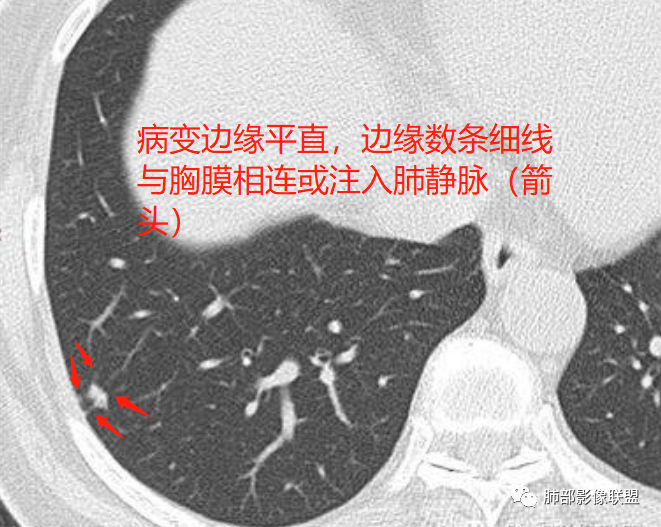

2、病灶边缘多平直,大部分呈三角形,部分呈椭圆形;

3、病灶边缘见一条或数条细线与胸膜相连。

如图所示:

长径均小于12mm。典型的形状为三角形,也可以为梭形、圆形或椭圆形。诊断的关键在于见到1-5条细线与胸膜、叶间胸膜或静脉相连,有时状如坐落于电路板的“二极管”,但以薄层CT显示为佳。有作者病理对照线状影为小叶间隔,有作者病理对照为淋巴管。其实不矛盾,因为淋巴管走行于小叶间隔内。

诊断肺内淋巴结最关键指出在于薄层扫描见到细线状影与胸膜、叶间胸膜及肺静脉相连。